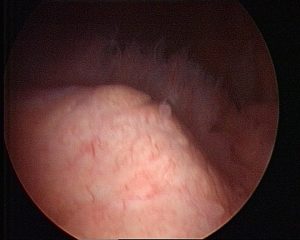

Abb.5 intraoperativer Situs bei unspezifischer Detritussynovialitis

Bei einer Instabilität werden je nach Zerstörung von Knorpelmatrix proteolytischer Enzyme, z.B. Matrix-Metalloproteinase-13 durch Sekretion inflammatorischer Zytokine (z.B. Interleukin 1) freigesetzt. Die Entzündungsreaktion zeigt sich als feingranuläre oder feinvillöse bis zur stärker zottigen villösen Hyperplasie als Detritussynovialitis oder lymphoplasmazelluläre Synovialitis (Abb.5). Bei letzterer kommt es zu einer geringgradig verbreiterten Deckzellschicht mit unterschiedlich starker Ansammlung von Lymphozyten auch perivaskulär. Unter den Lymphozyten ist das Verhältnis der CD 4+ zu CD 8+ T-Lymphozyten ausgewogen. Perivaskulär dominieren Plasmazellen und CD 20+ B-Lymphozyten (Abb.6).